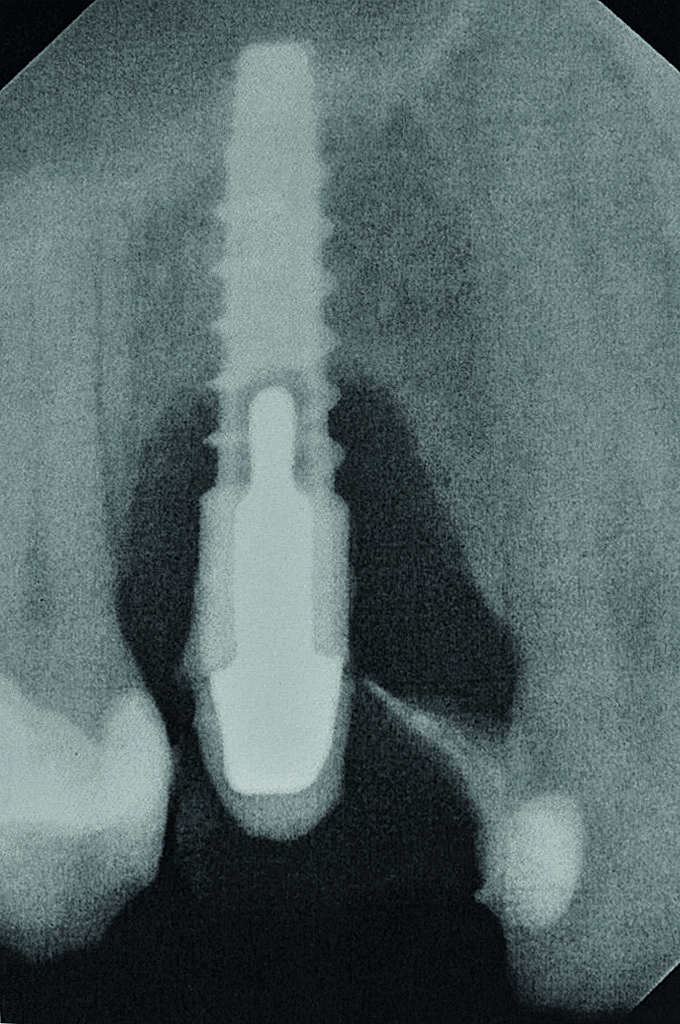

Fig. 2 : Radiographie de

l‘implant